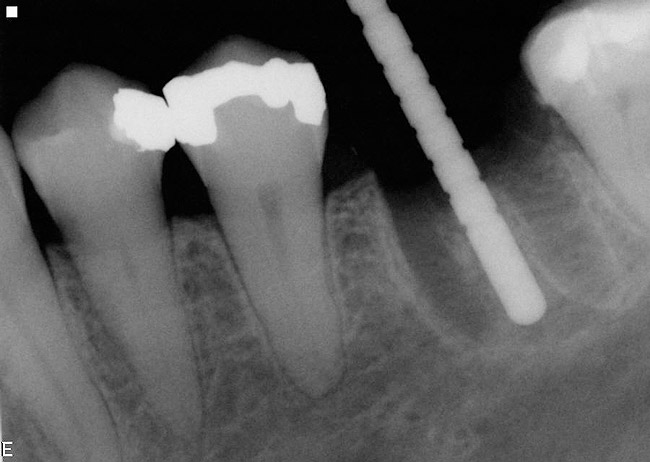

If the most crestal aspect of the interradicular bone is at least 3-mm-wide mesio-distally: A 2.2-mm-wide guide bur is drilled to the appropriate length, a guide pin is inserted, and a radiograph is taken (Figure 7). If necessary, the initial osteotomy is extended apically. A tapered osteotome is inserted into the osteotomy and moved mesio-distally and bucco-lingually to expand the osteotomy site. A 2.8-mm bur is used to prepare the osteotomy to depth, and a 2.8-mm-wide tapered osteotome is inserted in the osteotomy and once again utilized in mesio-distal and bucco-lingual directions to expand the osteotomy site. If the mesial and distal aspects of the interradicular bone are still intact at this point, a 3.5-mm bur is utilized to prepare the osteotomy to depth. A 3.5-mm-wide osteotome is inserted into the osteotomy and utilized in the manner already described. A decision is made as to whether to place a tapered implant with a 4.1-mm-wide base and a 6.5-mm-wide neck, or to use a 4.8-mm-wide bur and prepare the osteotomy to depth, in anticipation of placement of an implant with a 4.8-mm-wide parallel wall body and a 6.5-mm-wide platform. The chosen implant is inserted into the osteotomy (Figure 8), appropriate regenerative materials are placed, and the flaps are sutured. Following maturation of the regenerating hard tissues, the implant is ready for restoration (Figure 9). A radiograph taken 54 months after implant restoration demonstrates stability of the peri-implant crestal bone (Figure 10).